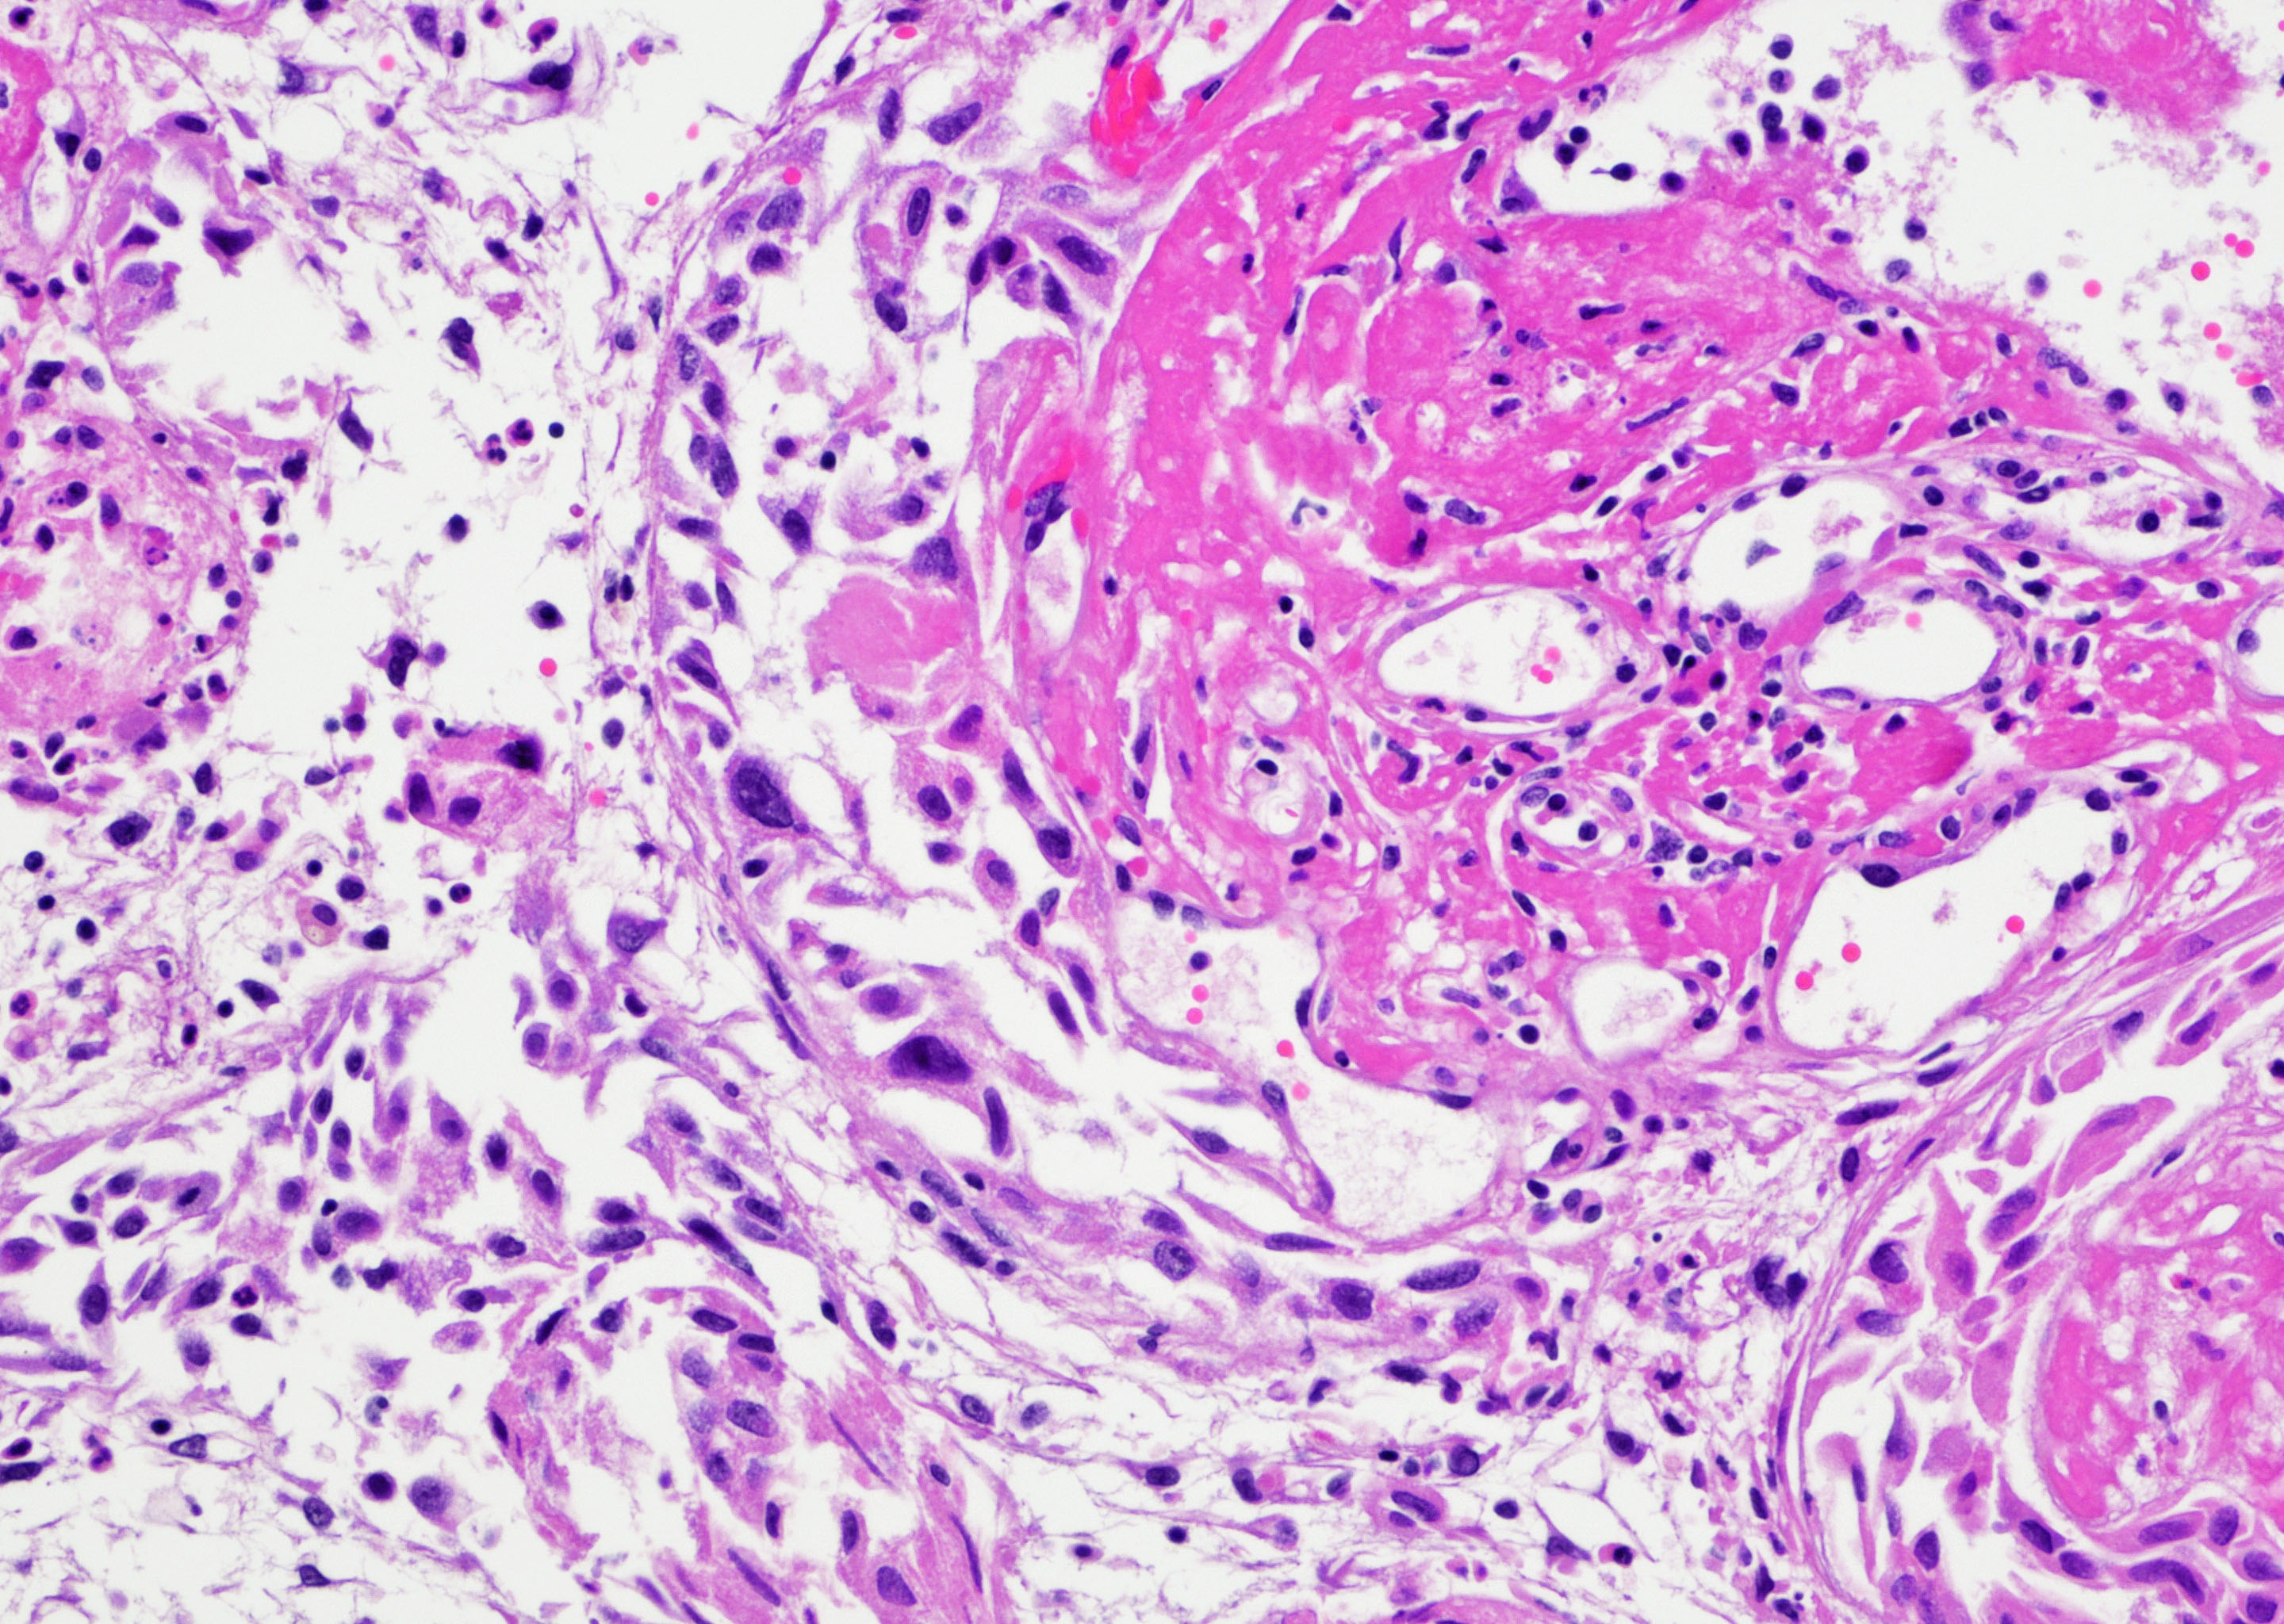

- Vessels with fibrin thrombi, fibrinoid vascular necrosis, vascular congestion, thickened walls, endothelial proliferation and telangiectasia

- Acute and chronic inflammation

- Reactive multinucleated stromal fibroblasts with smudgy nuclei

- Fibrosis and edema

- Hemorrhage and hemosiderin

- Pseudocarcinomatous urothelial hyperplasia: variable sized urothelial cords and nests with rounded or irregular edges present in the lamina propria and enclose dilated blood vessels with fibrin deposition (Am J Surg Pathol 2008;32:92)

- Acute phase: edematous, congested and telangiectatic vessels, acute and chronic inflammatory infiltrate, atypical stromal cells with multinucleated forms

- Chronic phase: atrophic urothelium, atrophic smooth muscle layer, collagen deposition (fibrosis) (Am J Surg Pathol 2004;28:909)

Microscopic (histologic) images

Contributed by Y. Albert Yeh, M.D., Ph.D. and Jennifer Lee, M.D.

- Comment: There is a history of radiation therapy per the medical record. The transurethral resection of the bladder lesion shows fragments of urothelial mucosa with total and partial denudation of urothelium. The urothelial lining cells show reactive changes. There is marked edema, hemorrhage and mixed inflammatory infiltrate composed predominantly of neutrophils and lymphocytes in the lamina propria. Reactive multinucleated stromal fibroblasts are seen. Telangiectatic vessels with fibrinoid necrosis and intravascular fibrin deposition are seen. Anastomosing cords and nests of urothelial cells encircling the vessels with fibrin deposition is evident. Urothelial cells with hyperchromatic nuclei, increased nuclear to cytoplasmic ratio and prominent nucleoli are seen. These features are consistent with radiation cystitis with pseudocarcinomatous urothelial hyperplasia. Muscularis propria is not identified in this specimen.

A 68 year old man presented with hematuria and dysuria. He has a medical history of prostate cancer that was treated with radiation therapy. Cystoscopy revealed hemorrhage in the right bladder wall. A transurethral resection of the lesion was performed. A photomicrograph is shown above. What is the diagnosis?

- Radiation cystitis with pseudocarcinomatous hyperplasia

C. Radiation cystitis with pseudocarcinomatous hyperplasia. Answers A, B and D are incorrect because anastomosing cords and nests of urothelial cells encircling ectatic vessels with intravascular and stromal fibrin deposition in a background of mixed inflammation are not present in these entities.